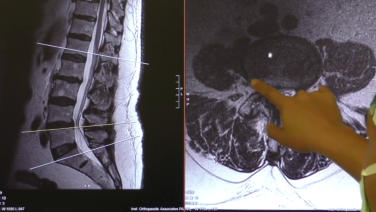

Anterior to Psoas Technique Case Presentation - Chadi Tannoury, MD